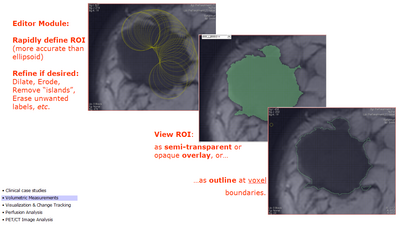

• in Editor module:

• use threshold paint to segment tumor; or

• use fastmarching with seeds in the tumor tissue

• erase any outlying pixels